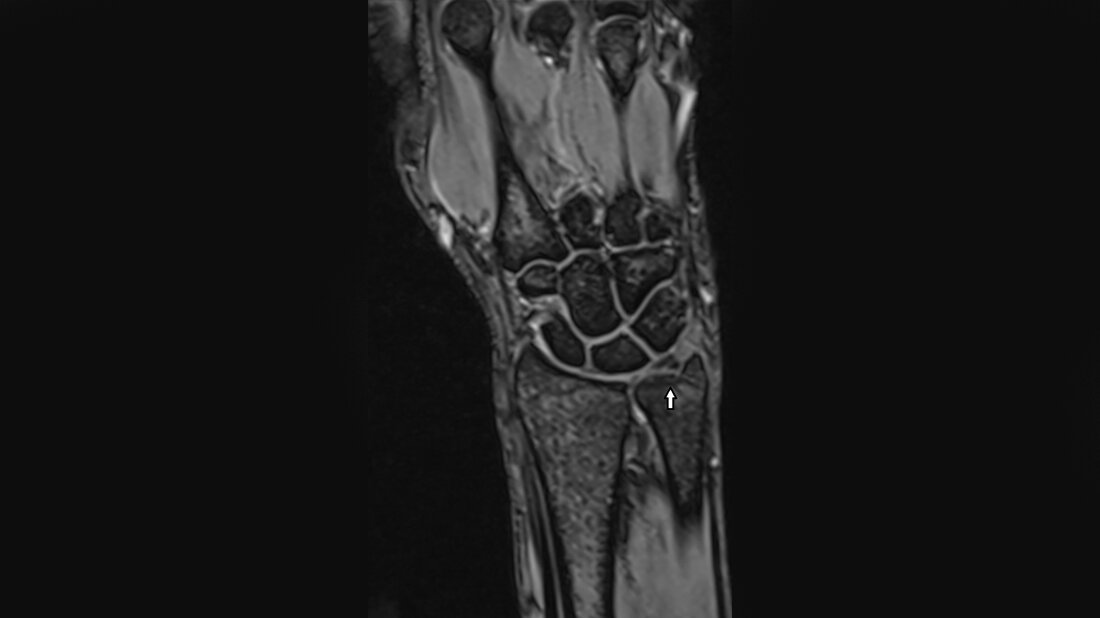

Das Ulna-Impaktions-Syndrom ist eine häufige Ursache des ulnarseitigen Handgelenkschmerzes. Die Palmer-Klassifikation differenziert die posttraumatischen von den degenerativen TFCC-Läsionen. Schon die Röntgenaufnahmen können die Ulna-Varianten nachweisen. Viele Patienten mit Ulna-Minus-Variante haben einen Morbus Kienböck.

Ulna impaction syndrome is a common source of ulnar-sided wrist pain. Palmer’s classification of TFCC lesions differentiates post-traumatic from degenerative tears. The standard X-ray projection can show the ulnar variance. Many patients with Kienböck’s disease have a ulna minus variant.